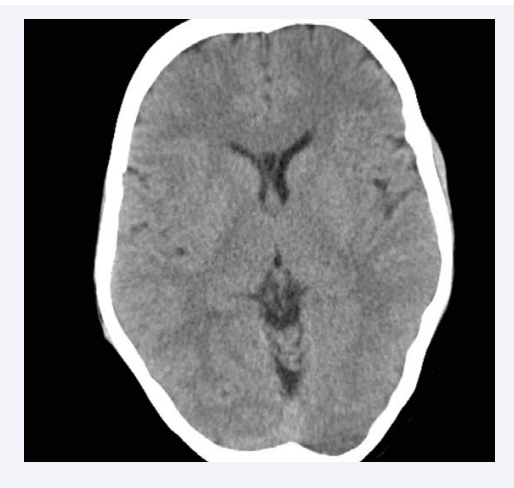

For determining and defining prevalence of normal and abnormal CSP we used the criteria that had been used in previous studies [8,18-20]. In these studies any CSP equal to or greater than 6 mm in length had been defined as abnormally large (Picture 1 & 2). CT scans of all patients and controls were reviewed, without knowledge of the diagnostic group by a neuroradiologist and a psychiatrist trained in neuroanatomy. Each rating was assigned on the basis of a consensus between the two examiners.

C. T. scan of an alcohol dependent patient showing abnormal  CSP (Length 9.6mm, Width 4.7mm, Width of septum 1.2mm)

Figure 2: C. T. scan of an alcohol dependent patient showing abnormal CSP (Length 9.6mm, Width 4.7mm, Width of septum 1.2mm)

Abbreviation: CSP: Cavum Septum Pellucidum